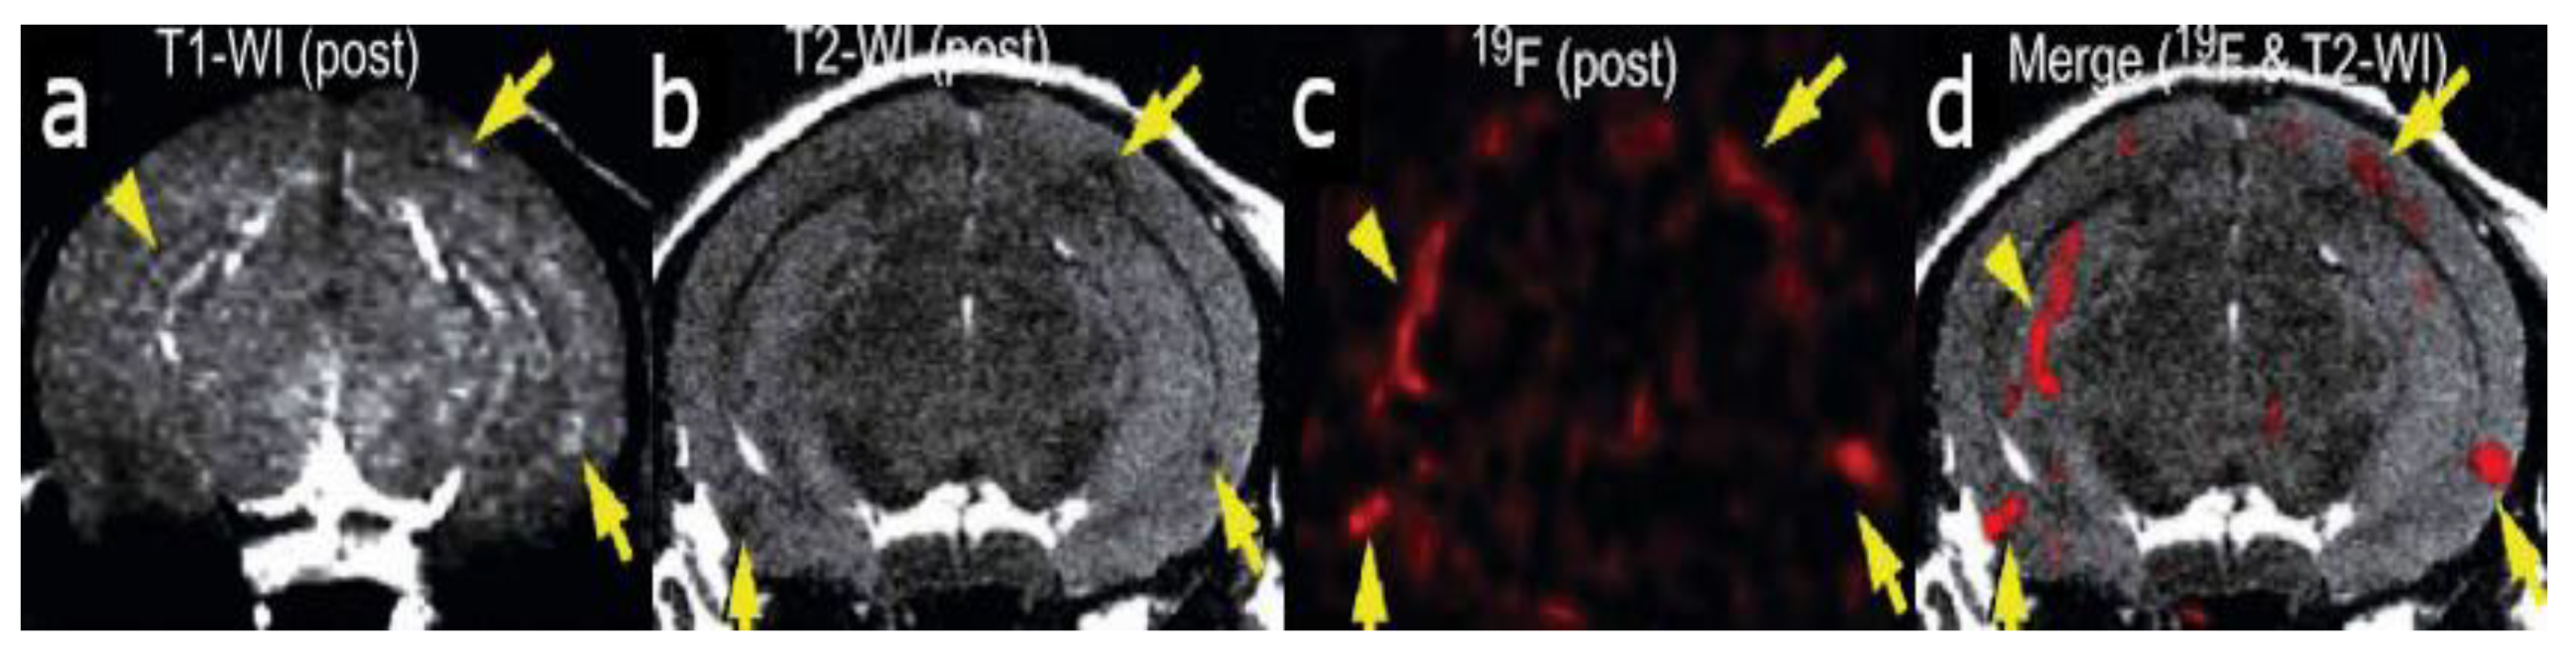

Figure 1.

In vivo detection of amyloid plaques (indicated by arrowheads and arrows) in the brain of a Tg2576 mouse after injection with (E,E)-1-fluoro-2,5-bis(3-hydroxycarbonyl-4-hydroxy)styryl-benzene (FSB) [14]. (a) T1-weighted 1H imaging of the mouse brain. (b) T2-weighted image of the same slice indicating the position of the amyloid-beta plaques. (c) 19F MRI image of the mouse brain after FSB injection. (d) 19F-FSB image overlaid on top of the high-resolution T2-weighted 1H image. Images are reprinted with permission from the publisher [14].